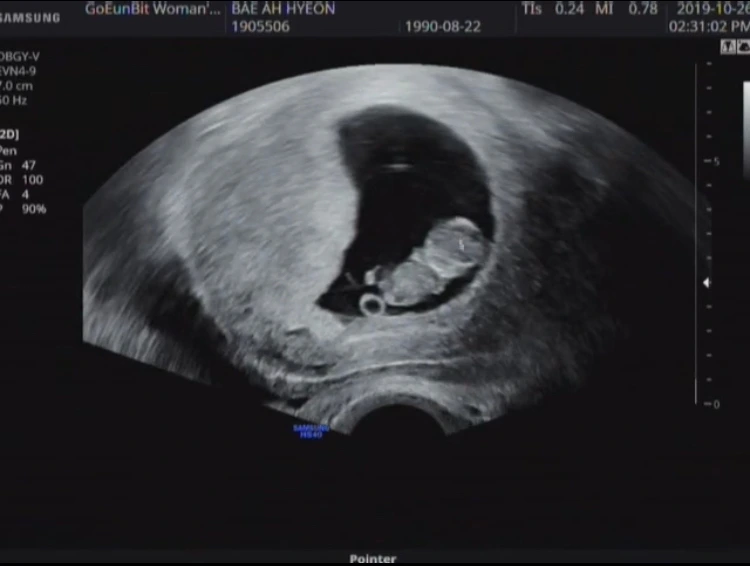

아직까지는 성별을 알 수 없는 임신 8주, 젤리곰 상태

임신 12주차에 병원 정기점검을 갔을 때를 잊을 수가 없는데 초음파를 보던 주치의의 표정과 멘트가 인상적이었다.

동공에는 지진이 났고, "여기 뭐가 보이네요. 괜찮으시겠어요?"

'여기 뭐가 보인다'는 말은 딸이 아니라 아들이라는 소리. 그런데 '괜찮으시겠어요?'는 어떤 의미인지 모르겠더라. 그래서 난 정말 순진무구하게 '왜요?' 라고 물어봤는데 주치의는 그냥 웃어넘기며 살짝 남편을 위로해줬다.

머지않아 곧 이유를 알게 됐다. 뱃속에 있는 아기 성별을 알릴 때마다 많은 사람들이 같은 반응을 보였기 때문이었다.

과거 남아선호사상이 지배적이었을 당시 제정된 법 조항인 것으로 추측되는데, 요즘은 보통 임신 12~16주 쯤이 되면 대략 성별을 알 수 있다. 병원에서는 여전히 성별을 명확히 언급하지 않지만, 딸이면 '엄마 닮았다', 아들이면 '아빠 닮았다'라고 우회적으로 알려주곤 한다.